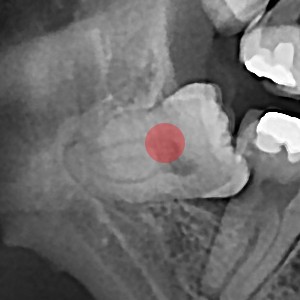

사랑니발치 부분 매복 사랑니